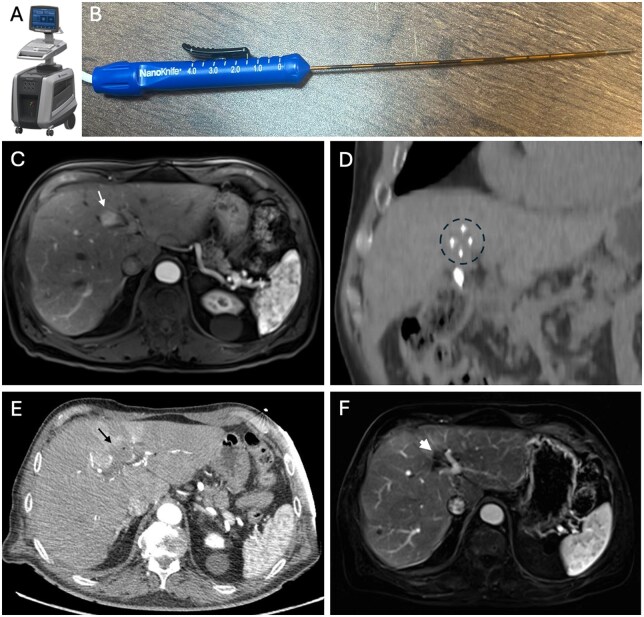

影像引导下的微创肿瘤消融技术是治疗各种不可切除软组织肿瘤的安全、有效的方法。标准的热消融方法包括射频消融、微波消融和冷冻消融。然而,新的非热和/或非侵入性消融技术现在可作为治疗软组织肿瘤的替代选择,特别是那些靠近关键结构或易受热能吸收效应影响的软组织肿瘤。本文讨论了四种新兴的消融技术:不可逆电穿孔、脉冲电场、高强度聚焦超声和组织切片法。虽然评估这些消融技术的安全性和有效性的临床试验还处于早期阶段,但初步结果在治疗不同阶段的各种癌症方面是有希望的。这些包括与化疗和免疫治疗联合使用时的潜在协同效应。

Minimally invasive image-guided tumor ablation techniques have been established as safe, effective methods to treat a variety of unresectable soft tissue tumors. Standard thermal ablation methods include radiofrequency ablation, microwave ablation, and cryoablation. However, newer non-thermal and/or non-invasive ablation techniques are now available as alternative options to treat soft tissue tumors, particularly those that are near critical structures or otherwise susceptible to thermal energy sink effects. The 4 types of emerging ablation techniques discussed in this review are as follows: irreversible electroporation, pulsed electric field, high-intensity focused ultrasound, and histotripsy. While the clinical trials evaluating the safety and efficacy of these ablation techniques are in their early stages, initial results are promising in the treatment of various cancers at different stages. These include potential synergistic effects when combined with chemotherapy and immunotherapy.